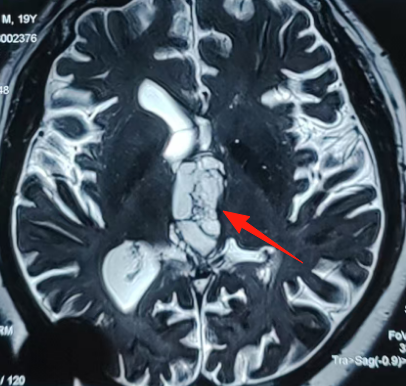

19岁的生命遭遇严峻挑战,巨大三脑室肿瘤位于大脑中心深部,血供丰富、质地坚韧,与三脑室壁、丘脑、深部血管黏连紧密,手术异常艰难。巴教授主刀,中外专家通力协作,经胼胝体-脉络膜裂入路安全全切肿瘤,为年轻的生命重燃希望!

19岁少年飞宇,一个40×25×31mm的巨大肿瘤已完全占据第三脑室,从室间孔向下压迫中脑。三脑室,这个前后仅2.5-3cm、宽约0.5cm的狭小腔隙,却密集分布着维系生命的关键结构。

- 1. 第三脑室位于大脑中心深部。到达目标需要切开胼胝体、分离脉络膜裂、进入三脑室顶部。巨大肿瘤本身就占据空间,操作通道更加狭窄和深长。手术器械的活动范围受限,操作精确度要求极高,手部微小震颤会被放大,可能误伤周围关键结构。

- 2. 脉络膜裂是位于穹窿和丘脑之间、脉络丛附着处的一条潜在的裂隙。巨大肿瘤导致其扭曲、粘连、被挤压变薄。安全有效地打开此裂隙而不损伤下方的深部静脉系统和丘脑至关重要,操作需在极其有限的深部空间内精细进行。分离不当易撕裂脉络膜或损伤其下方的静脉系统(如丘纹静脉),导致灾难性出血或静脉性梗死。

- 3. 巨大肿瘤本身有丰富血供,深部止血困难,大量出血迅速充满术野,干扰操作并增加损伤风险。而飞宇的肿瘤质地坚韧似橡皮膏,与三脑室壁、丘脑、深部血管黏连紧密,只能分块切除或借助CUSA,强行牵拉易导致出血或伤及周围结构。